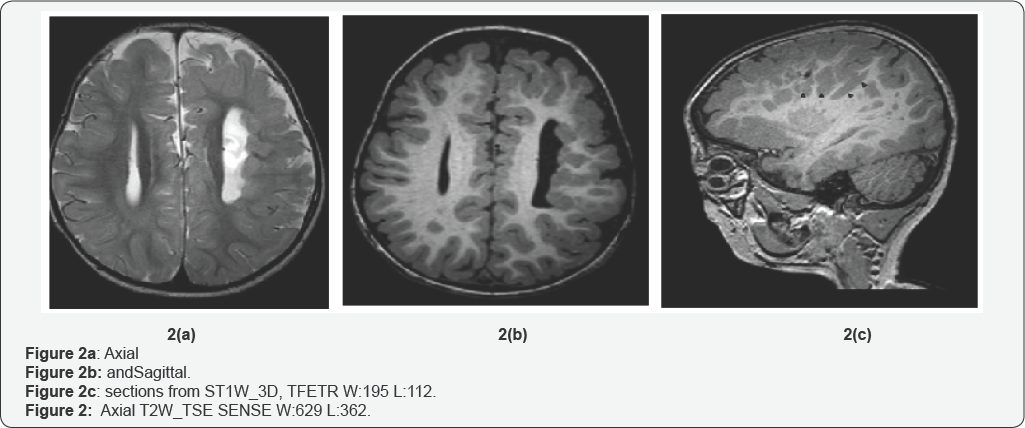

The patient had two MRI studies, at age of one month and age of 2 years. Both studies showed the same typical features of Delleman syndrome. He had polymicrogyria in the left frontal and parietal lobes (Figure 1a & 1b), Migrational anomalies in the form of heterotopic grey matter in the ependymal lining of left lateral ventricles, nodular heterotopias in the frontal and occipital lobes, more posteriorly (Figure 2a, 2b & 2c), and bands of heterotopic grey matter which were seen radiating from the periventricular area to the occipital cortex (Figure 3). The left lateral ventricle was slightly prominent. The above findings were confined to the left cerebral hemisphere. The right cerebral hemisphere was spared. Corpus callosum agenesis was also noted, without midline cyst or lipoma. The tectum was giant, slightly flexed anteriorly, making the aqueduct nearly horizontal. The vermis was absent and there was large posterior fossa cyst, communicating to the fourth ventricle (Figure 3). The left eye was small (microphthalmia) and there was a multiloculated cyst in the roof of left orbit anteriorly (Figure 4). The above findings are typical in a patient with the oculocerebrocutaneous syndrome [4-6].

The forebrain malformation includes frontal predominant polymicrogyria; periventricular nodular heterotopia; complete or partial agenesis of the corpus callosum, sometimes associated with interhemispheric cysts; and enlarged third and lateral ventricles, which can be complicated by hydrocephalus. The mid-hindbrain malformation consisted of a giant tectum, absent vermis, and large posterior fossa fluid collection. The midbrain tegmentum sometimes flexed forward, making the aqueduct nearly horizontal. The giant and dysplastic tectum was rotated upward well above the normal position and appeared to form an arch over the enlarged lower aqueduct in 7/8 patients. The cerebellar hemispheres were missing or hypoplastic with a dysplastic foliar pattern in 7/8 patients. The fourth ventricle communicated widely with a large posterior fossa fluid collection, sometimes associated with an occipital meningocele.